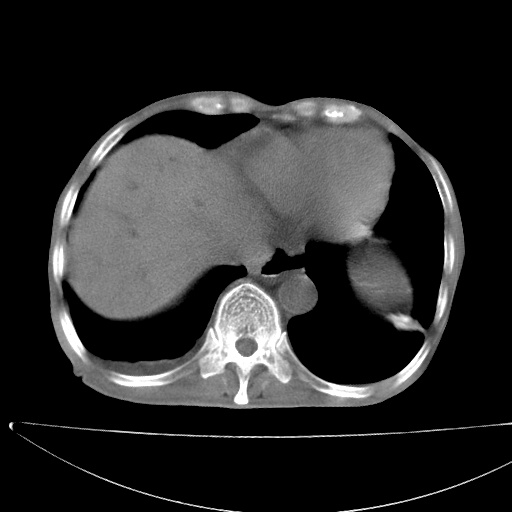

患者男70岁,上腹部不适1月。8年前有胃癌手术史。余病史不祥。

考虑胃癌复发并小网膜淋巴结转移侵及肝脏胆总管梗阻

考虑胃癌复发并腹腔内淋巴结转移。

1)胃癌术后,复发不排除。

2)肝脏转移瘤。

3)肝脏钙化灶。

4)胆囊增大。

5)腹膜后多发性淋巴结转移。

6)腹水。

7)右侧少量胸水。

建议:增强扫描。

考虑胃窦癌肝门转移

考虑胃癌复发并腹腔内淋巴结转移,胆总管受侵。

考虑胃窦癌肝门区淋巴结转移!

1)胃癌术后,不排除复发可能。2)考虑肝脏及腹膜后淋巴结转移瘤。3)肝内胆管扩张,胆囊增大。4)肝内胆管结石(或钙化)。5)脾脏钙化灶。6)腹水。7)右侧少量胸腔积液。

建议:行ct增强扫描检查。

1、胃癌根治胃空肠吻合术后,残胃癌?

2、肝门区占位性病变并胆道上段梗阻(肝内胆管扩张、胆囊增大),考虑肝门区淋巴结转移累及胆总管,建议ct增强扫描;

3、右侧胸腔少量积液、少量腹水;

4、肝右叶胆管结石。